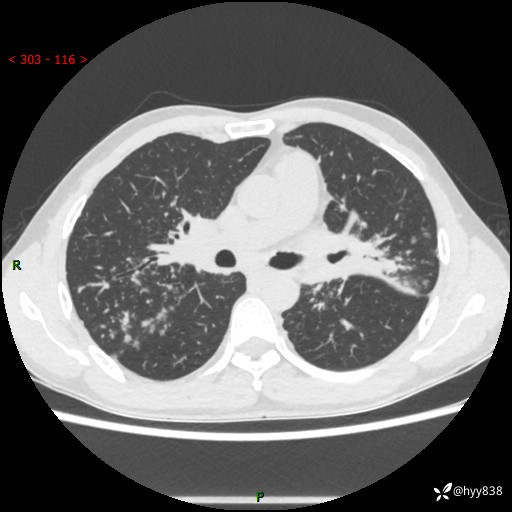

中年男性,咳嗽咳痰1月余。细看:肺、肺门、气管,貌似都有问题---(有结果)

现病史:患者于1个月前受凉后出现间断性咳嗽,伴白色泡沫样痰,无发热寒战、咯血、胸痛胸闷、恶心呕吐、呼吸困难等特殊不适,起初未予特殊处理,后患者就诊当地中医医院,查胸部CT提示支气管炎并双肺感染性病变,经抗感染(哌拉西林舒巴坦),止咳化痰(溴己新、三拗片)等治疗后,患者自诉咳嗽咳痰症状较前缓解,未诉发热等其他特殊不适,近期复查CT提示“肺部感染灶未见消退,双侧肺门增大,双肺散在小结节”,今为求进一步诊治,前来我院就诊,门诊以“肺部感染”收住入院。 患者自起病来精神、食欲、睡眠尚可,大小便正常,体力、体重无明显变化。

胸部CT平扫+增强(两期)